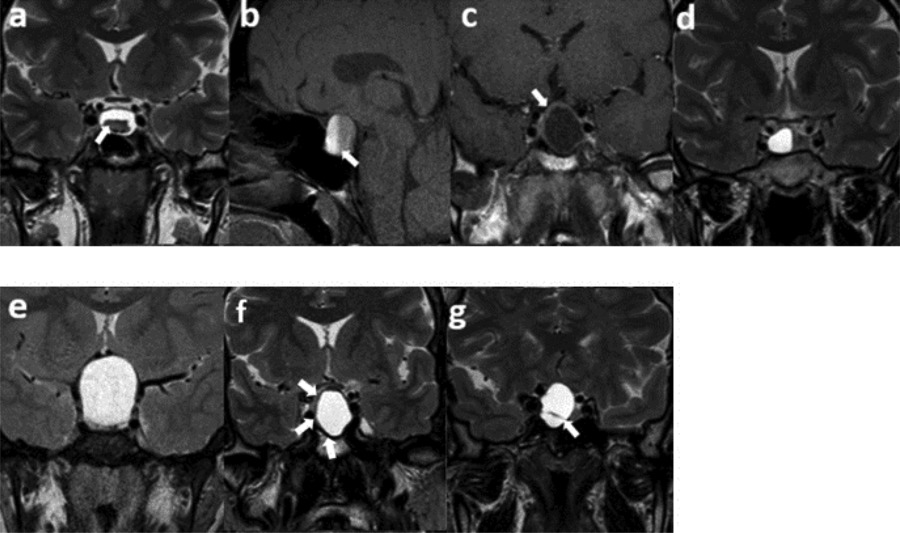

Figure 1

Semantic features. (a) An intracystic nodule on T2WI, (b) intralesional fluid–fluid level on SPIR T1WI, (c) ≥2 mm thickness of contrast-enhancing wall, (d) off-midline location, (e) suprasellar extension, (f) hypointense rim on T2WI, (g) intralesional septation on T2WI.